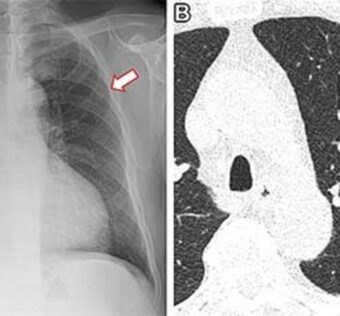

![]() AI’s Role in Identifying Non-Smokers’ Lung Cancer Risk

DistilINFO Hospital IT - (Thursday November 23, 2023) AI’s prowess predicts lung cancer risk in non-smokers through routine chest X-rays. The study unveils an advanced “CXR-Lung-Risk” model, identifying 28% of participants at significantly higher risk. Dr. Lu emphasizes its pivotal role amid… ![]() Real-time machine learning model to predict in-hospital cardiac arrest using heart rate variability in ICU